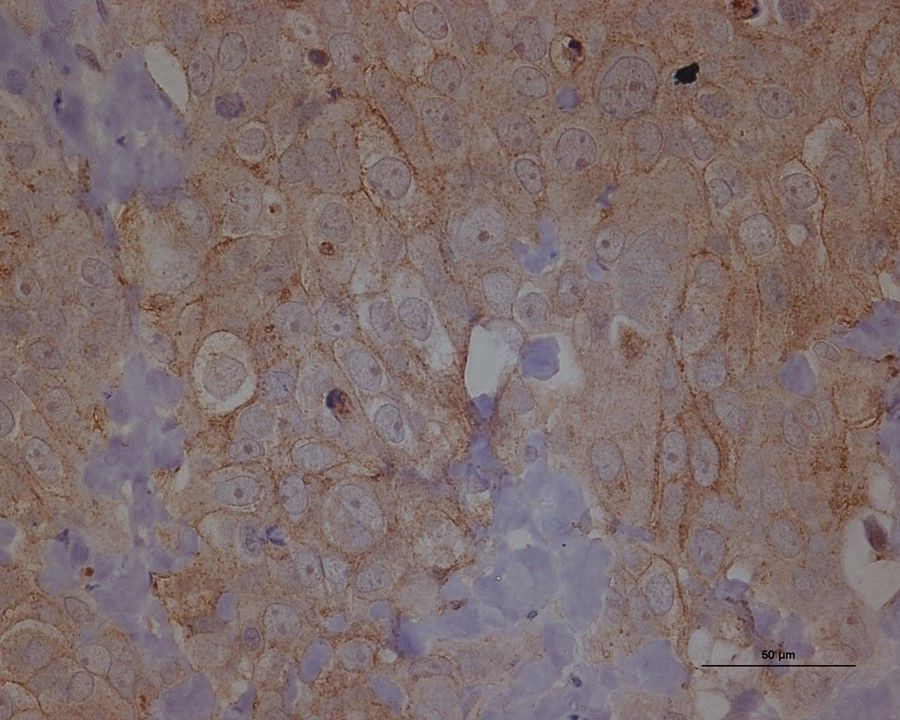

Los investigadores utilizaron microscopía de video de lapso de tiempo para observar cómo se movían las células, y encontraron que las células fuertemente adherentes durarían, moviéndose a secciones más rígidas, mientras que las células débilmente adherentes migrarían a tejidos más blandos.

Tras investigar varios mecanismos potenciales dentro de la célula que permiten este comportamiento, el equipo se centró en la contractilidad como marcador clave de su capacidad de adurotaxis. Modulando el número de motores de miosina activos dentro de la célula -un marcador de la capacidad contráctil- consiguieron que las células previamente duro-tácticas se alejaran del tejido más rígido, y que las células previamente aduro-tácticas y poco adherentes migraran hacia arriba en el gradiente de rigidez.